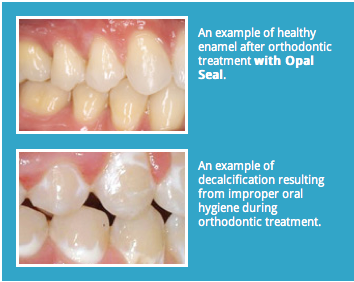

Poor oral hygiene is the major cause of decalcification. While white spots are not as noticeable between the teeth, it can be a problem. Have fruit juices in moderation.